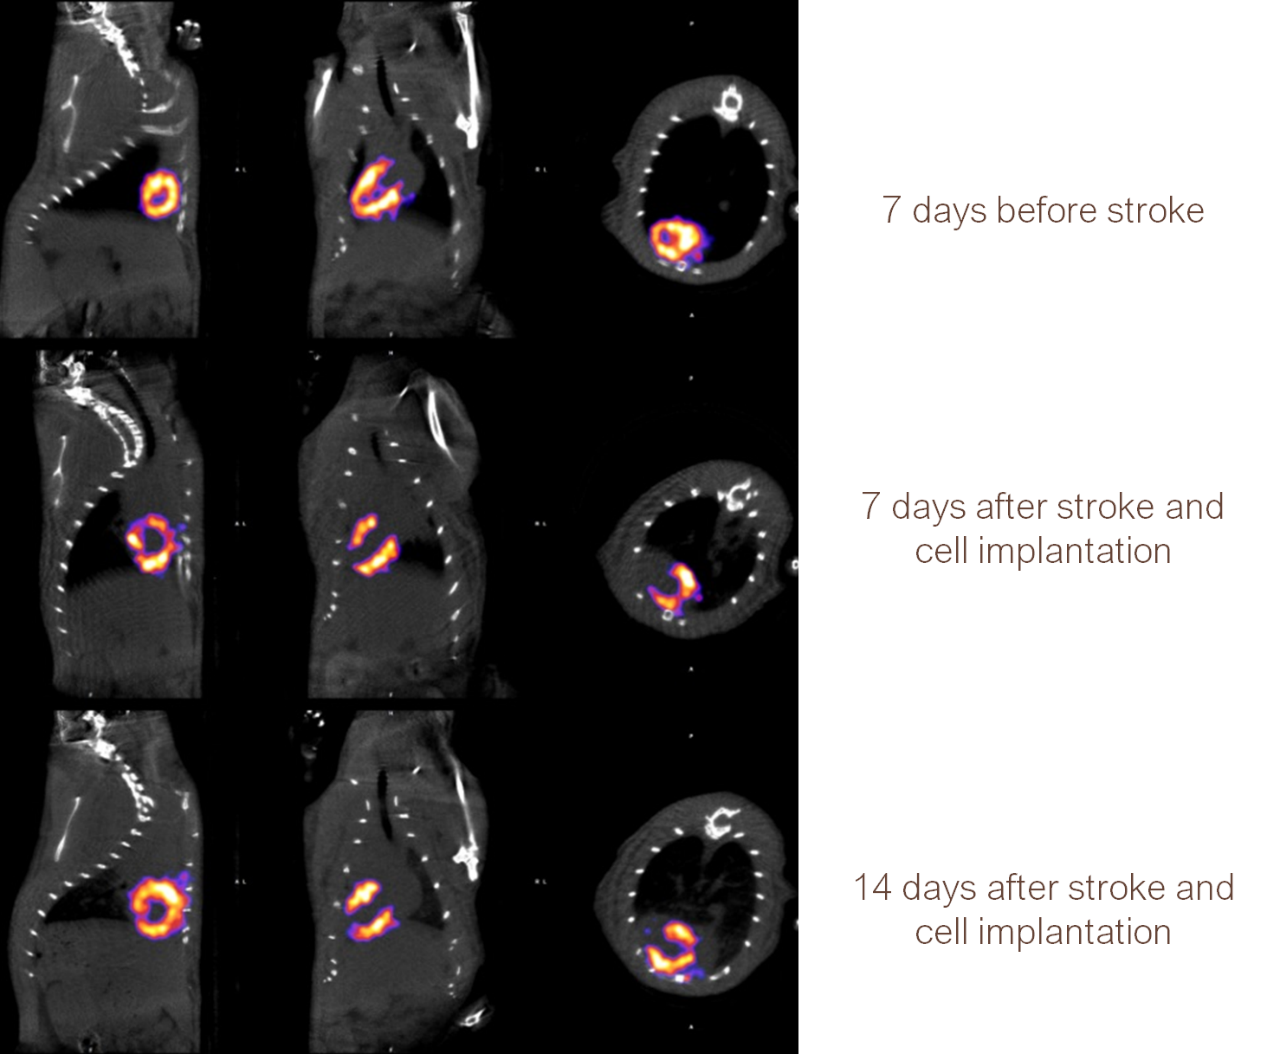

Myocardial SPECT imaging in mice: the drug 99mTc-MIBI reflected the myocardial blood perfusion volume at the time of injection, 63.27MBq (1.71mCi) @start acquisition, and the acquisition time was 40min.

The cardiac blood flow was observed before and after stroke and after medication in rat model of cardiovascular stroke.